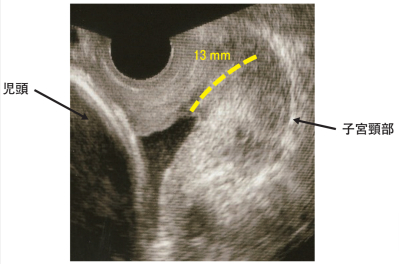

身長 154 cm、体重 46 kg(非妊時 40 kg)。体温 36.6 ℃、脈拍 72/分、整。胎位は頭位で推定胎児体重は 2,000 g。子宮に圧痛を認めない。腟鏡診にて腟内に少量の血液付着を認めるが、持続的な出血や羊水流出を認めない。 経腟超音波断層法検査所見及び胎児心拍数陣痛図を別に示す。